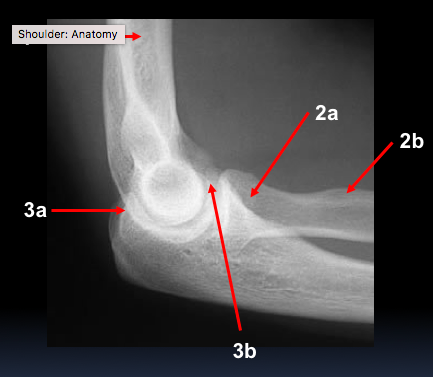

What are the labels?

1 - humerus

2a - radial head

2b - radial tuberosity

3a - olecranon

3b - coronoid process